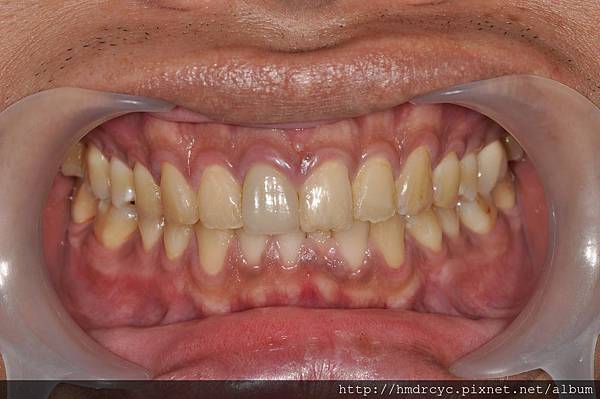

前金的C先生有相同問題

單純牙肉發炎沒有骨頭吸收

洗牙治療後 隔天牙肉消腫回到原本位置